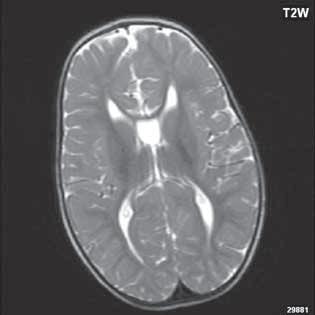

Abnormálně lokalizovaná šedá hmota mozková na základě poruchy migrace. Jedná se o šedou hmotu mozkovou v atypické lokalizaci. Může být dědičné etiologie, ale i na podkladě infekce, toxických vlivů. Morfologicky rozlišujeme periventrikulární nodulární (subependymální) formu, která je nejčastější, kdy nodul či noduly šedé hmoty se vyklenují do postranních komor či jsou k nim přilehlé, dále laminární formu (subcortical band heterotopia, „dvojitý kortex“), která je charakterizována laminárním pruhem šedé hmoty pod kůrou, od které je separována tenkým proužkem bílé hmoty (někdy je řazena jako mírná forma lissencefalie I) a subkortikální nodulární heterotopii (noduly zde mohou být značně rozsáhlé až imitující mozkový tumor). Marginální glioneurální heterotopie (leptomeningeální glioneurální heterotopie) není detekovatelná zobrazovacími metodami, jedná se o fokální nebo difuzní kolekci glioneurální tkáně na leptomeningách. Heterotopie jsou často asociovány s dalšími malformacemi CNS.

Zobrazení

CT je modalita málo senzitivní, prokáže ložiska denzity šedé hmoty mozkové, beze změn po aplikaci KL. MR je nejcitlivější zobrazovací metoda (optimální zobrazení šedé hmoty mozkové je technikou T1W + IR, naopak modalita FLAIR, velmi citlivá pro zobrazení změn bílé hmoty mozkové, nemá u heterotopie změny signálu nebo jen velmi diskrétní). Signálově ložiska heterotopie odpovídají šedé hmotě mozkové. Po aplikaci KL je beze

změn. Při ložiskové, subkortikální lokalizaci může být mozková kůra v jejich blízkosti zesílena, s projevy kortikální dysplazie.

Heterotopie šedé hmoty (subependymální forma) (šipka)

Obr. I.1.3c Heterotopie šedé hmoty (subependymální forma) (šipka)

Obr. I.1.3d Heterotopie šedé hmoty (subependymální forma); stejný pacient jako na obr I 1 3c

Obr. I.1.3e Heterotopie šedé hmoty (nodulární forma) (šipka)

Obr. I.1.3f Oboustranná subependymální heterotopie (šipky)